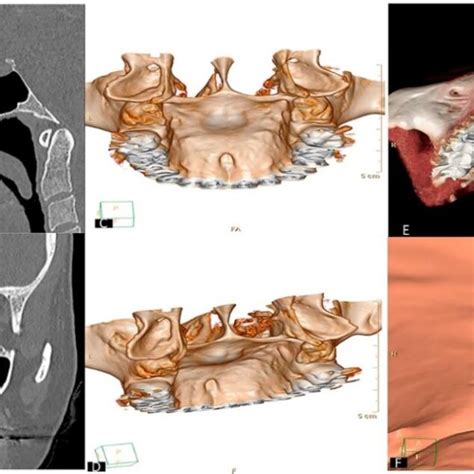

El diagnóstico de las exóstosis bucales se basa en la historia clínica, el examen físico y la evaluación de las características clínicas. Un torus mandibular se distingue por ser un bulto muy duro (óseo), generalmente bilateral y de crecimiento lento. De todos modos, la mejor forma de distinguirlo es acudiendo al dentista. Con un examen clínico y, si hiciera falta, una radiografía, confirmaremos que ese bulto duro es simplemente hueso (el torus) y no otra patología.